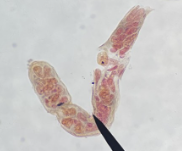

trematode miracidium

trematode redia

Trematode sporocyst